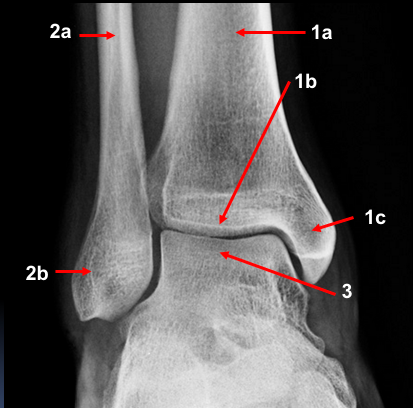

A 25 year old man presented to the ED with right ankle pain after a fall.

He was struggling to walk. His ankle was swollen and tender on examination. Movement was limited due to pain.

What can you see? What injuries are present?

A 30 year old woman presented to the ED with right ankle pain after a fall. She was struggling to walk. Her ankle was swollen and tender on examination. Movement was limited due to pain.

AP and lateral fibula:

What is a maisonneuve fracture?

A combination of a fracture of the proximal fibula together with an unstable ankle injury (widening of the ankle mortise on x-ray)